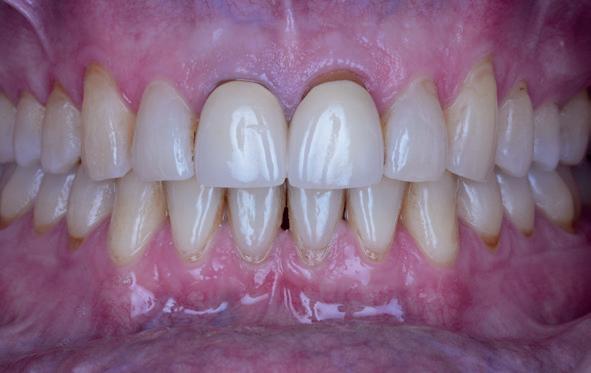

18. Etsbrug frontbeeld

19. Etsbrug palatinaal